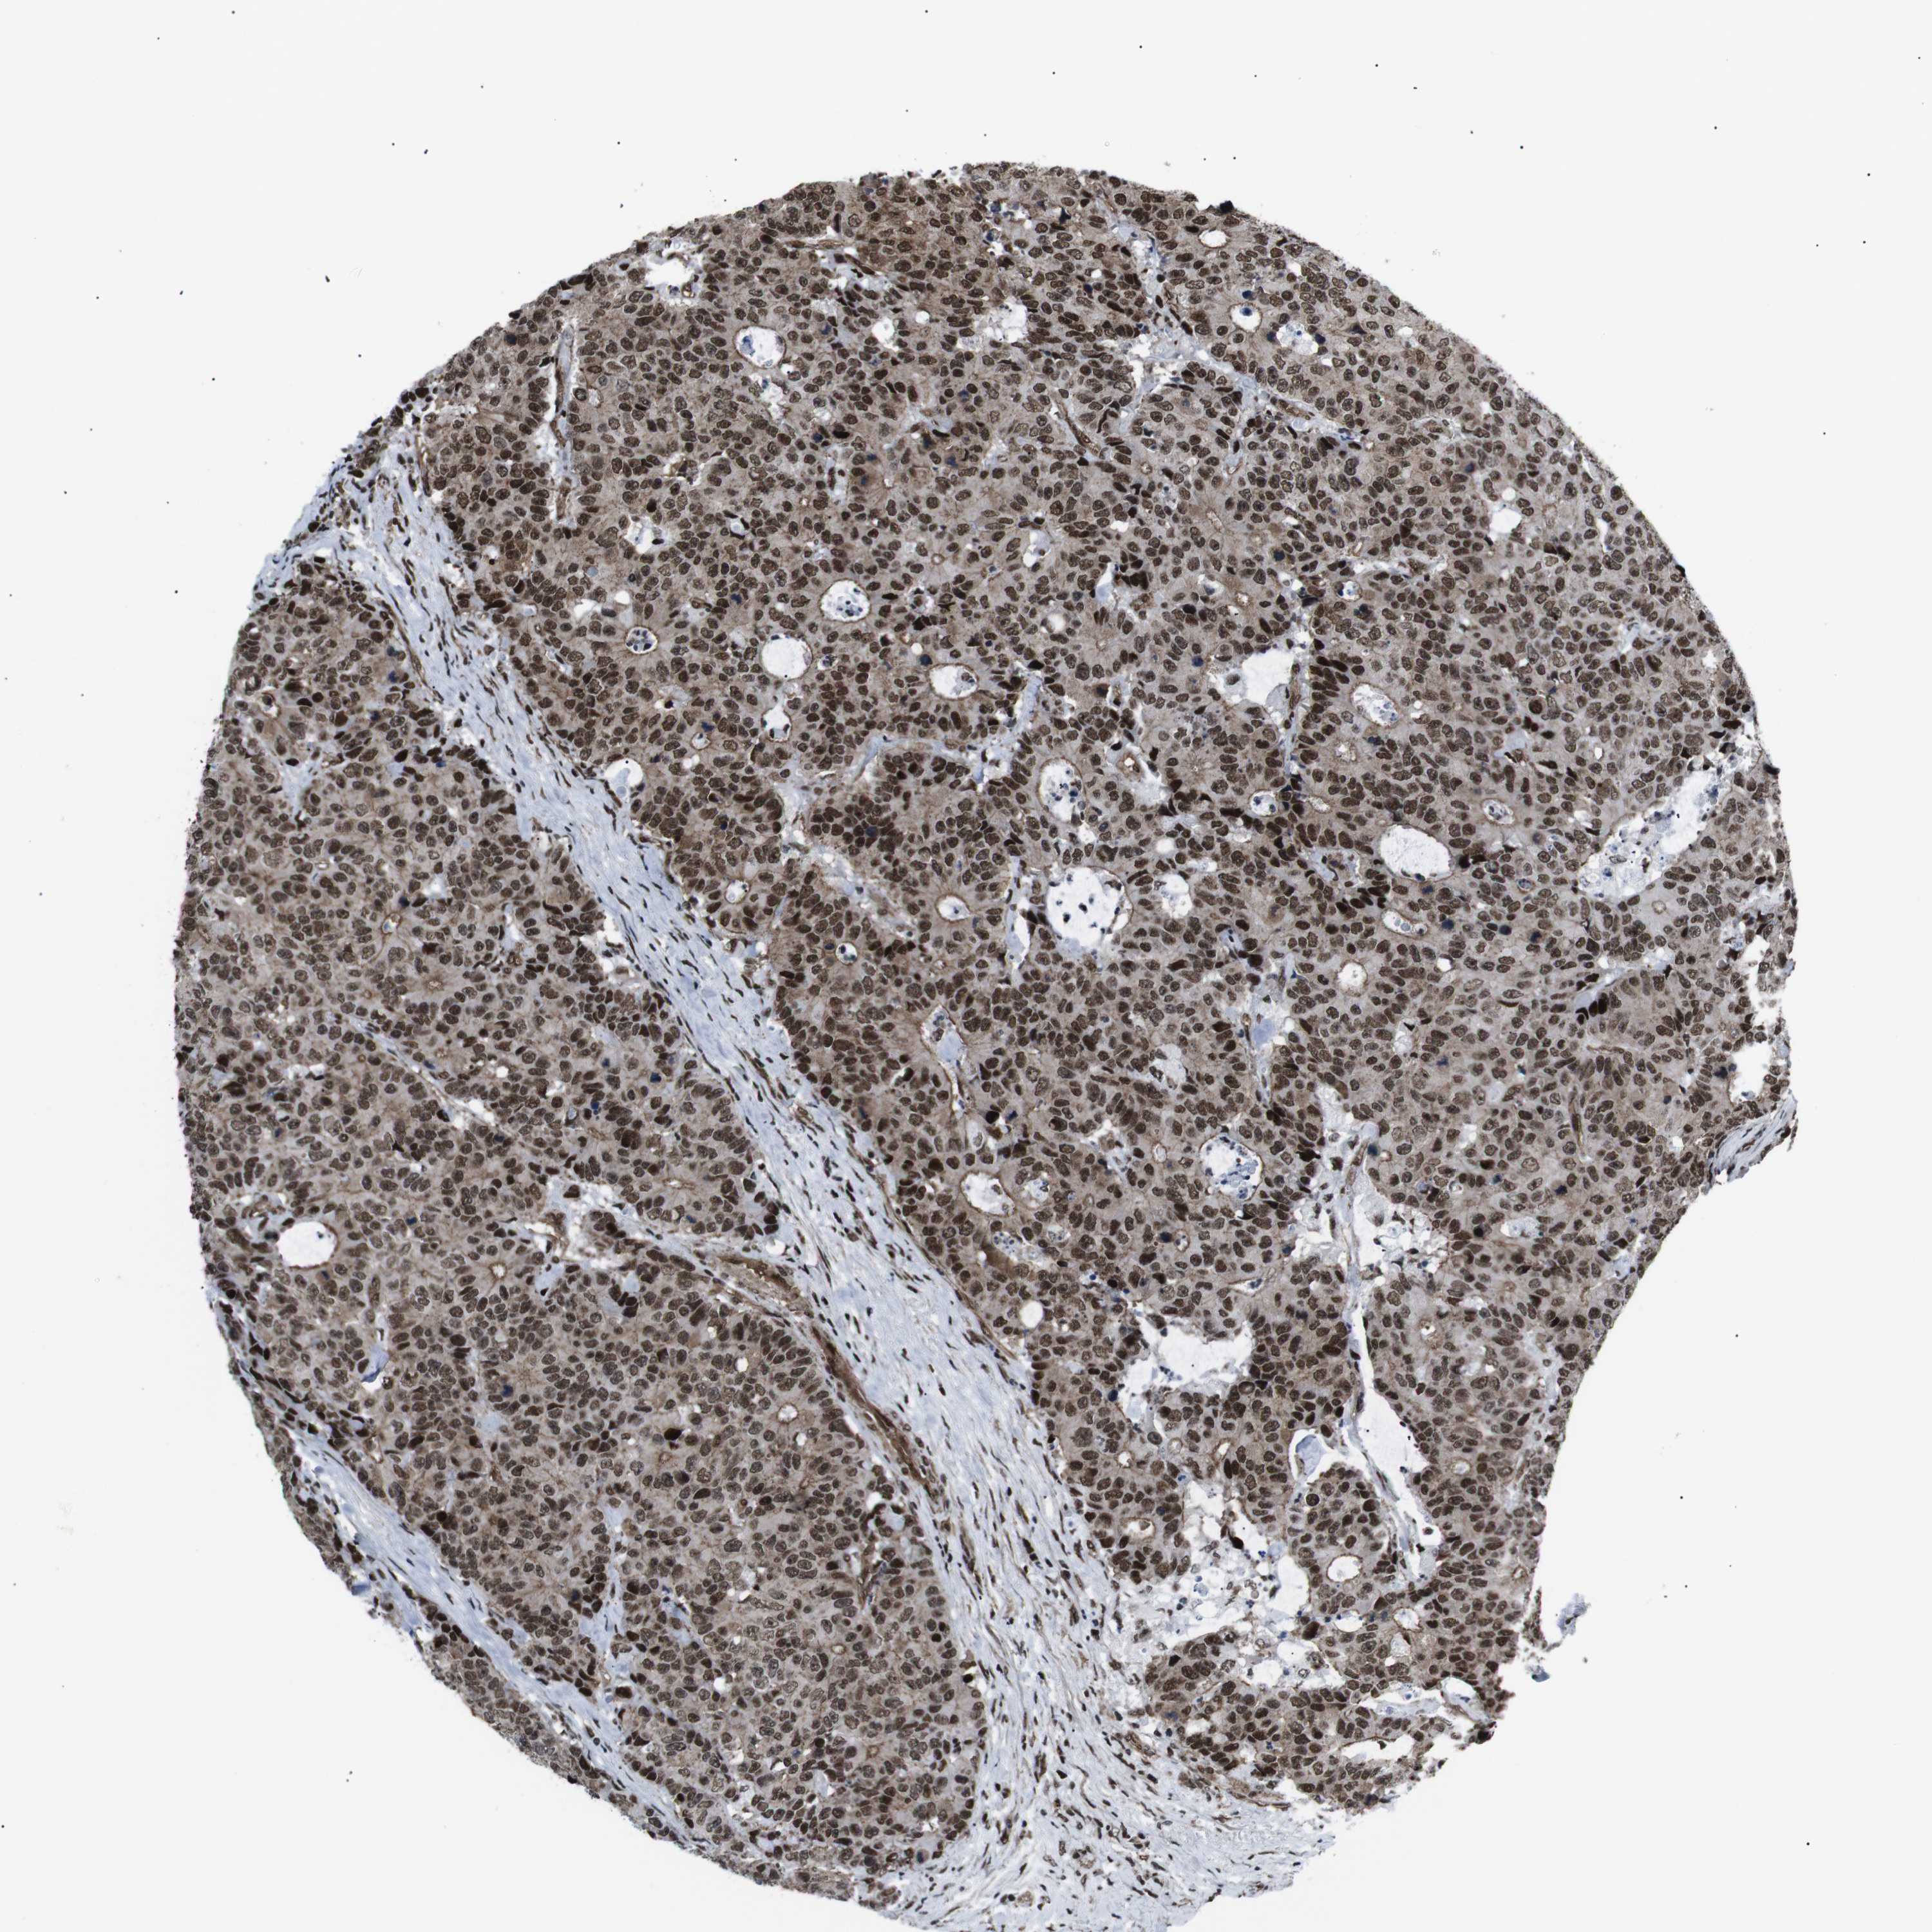

CANCER COLORECTAL CANCER Show tissue menu

Colorectal cancer

Human cancer

Rectum adenocarcinoma